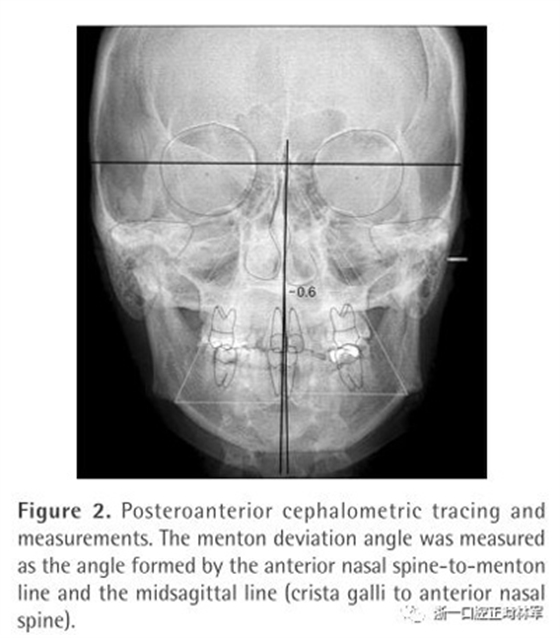

為了測量頦部偏移角度和唇線傾斜的關(guān)系,在拍正位片的時候,在兩個耳桿上都有金屬球來作為參考以確保FH平面和地面平行。頦部偏移角度為前鼻嵴-頦點連線與正中矢狀線的夾角(Figure 2)。